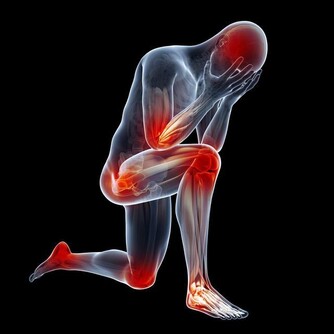

*****3.肢體麻木*****

患者在發病前會有臉部、舌頭、唇部麻木等表現,最明顯的還會出現嘴歪流口水等。有時患者一側的肢體會出現麻木,肢體不靈活,使不上勁。